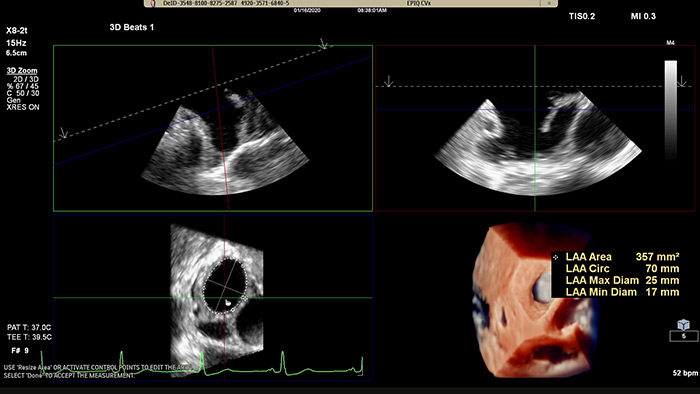

EPIQ CVx -TrueVue Glass with 3D Auto LAA

Rapidly acquire LAA orifice measurements in both traditional rendering or in TrueVue Glass rendering, with 3D Auto LAA